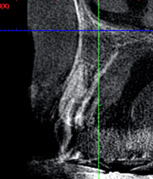

![]() |

治療前のCTです。根が残っています。 |